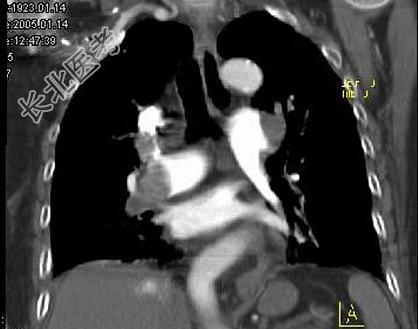

- 单项选择题82岁,女性, 突发右侧胸痛,呼吸急促, 行急诊CT检查,如图所示, 请选择最佳答案 ( )

D、肺动脉栓塞